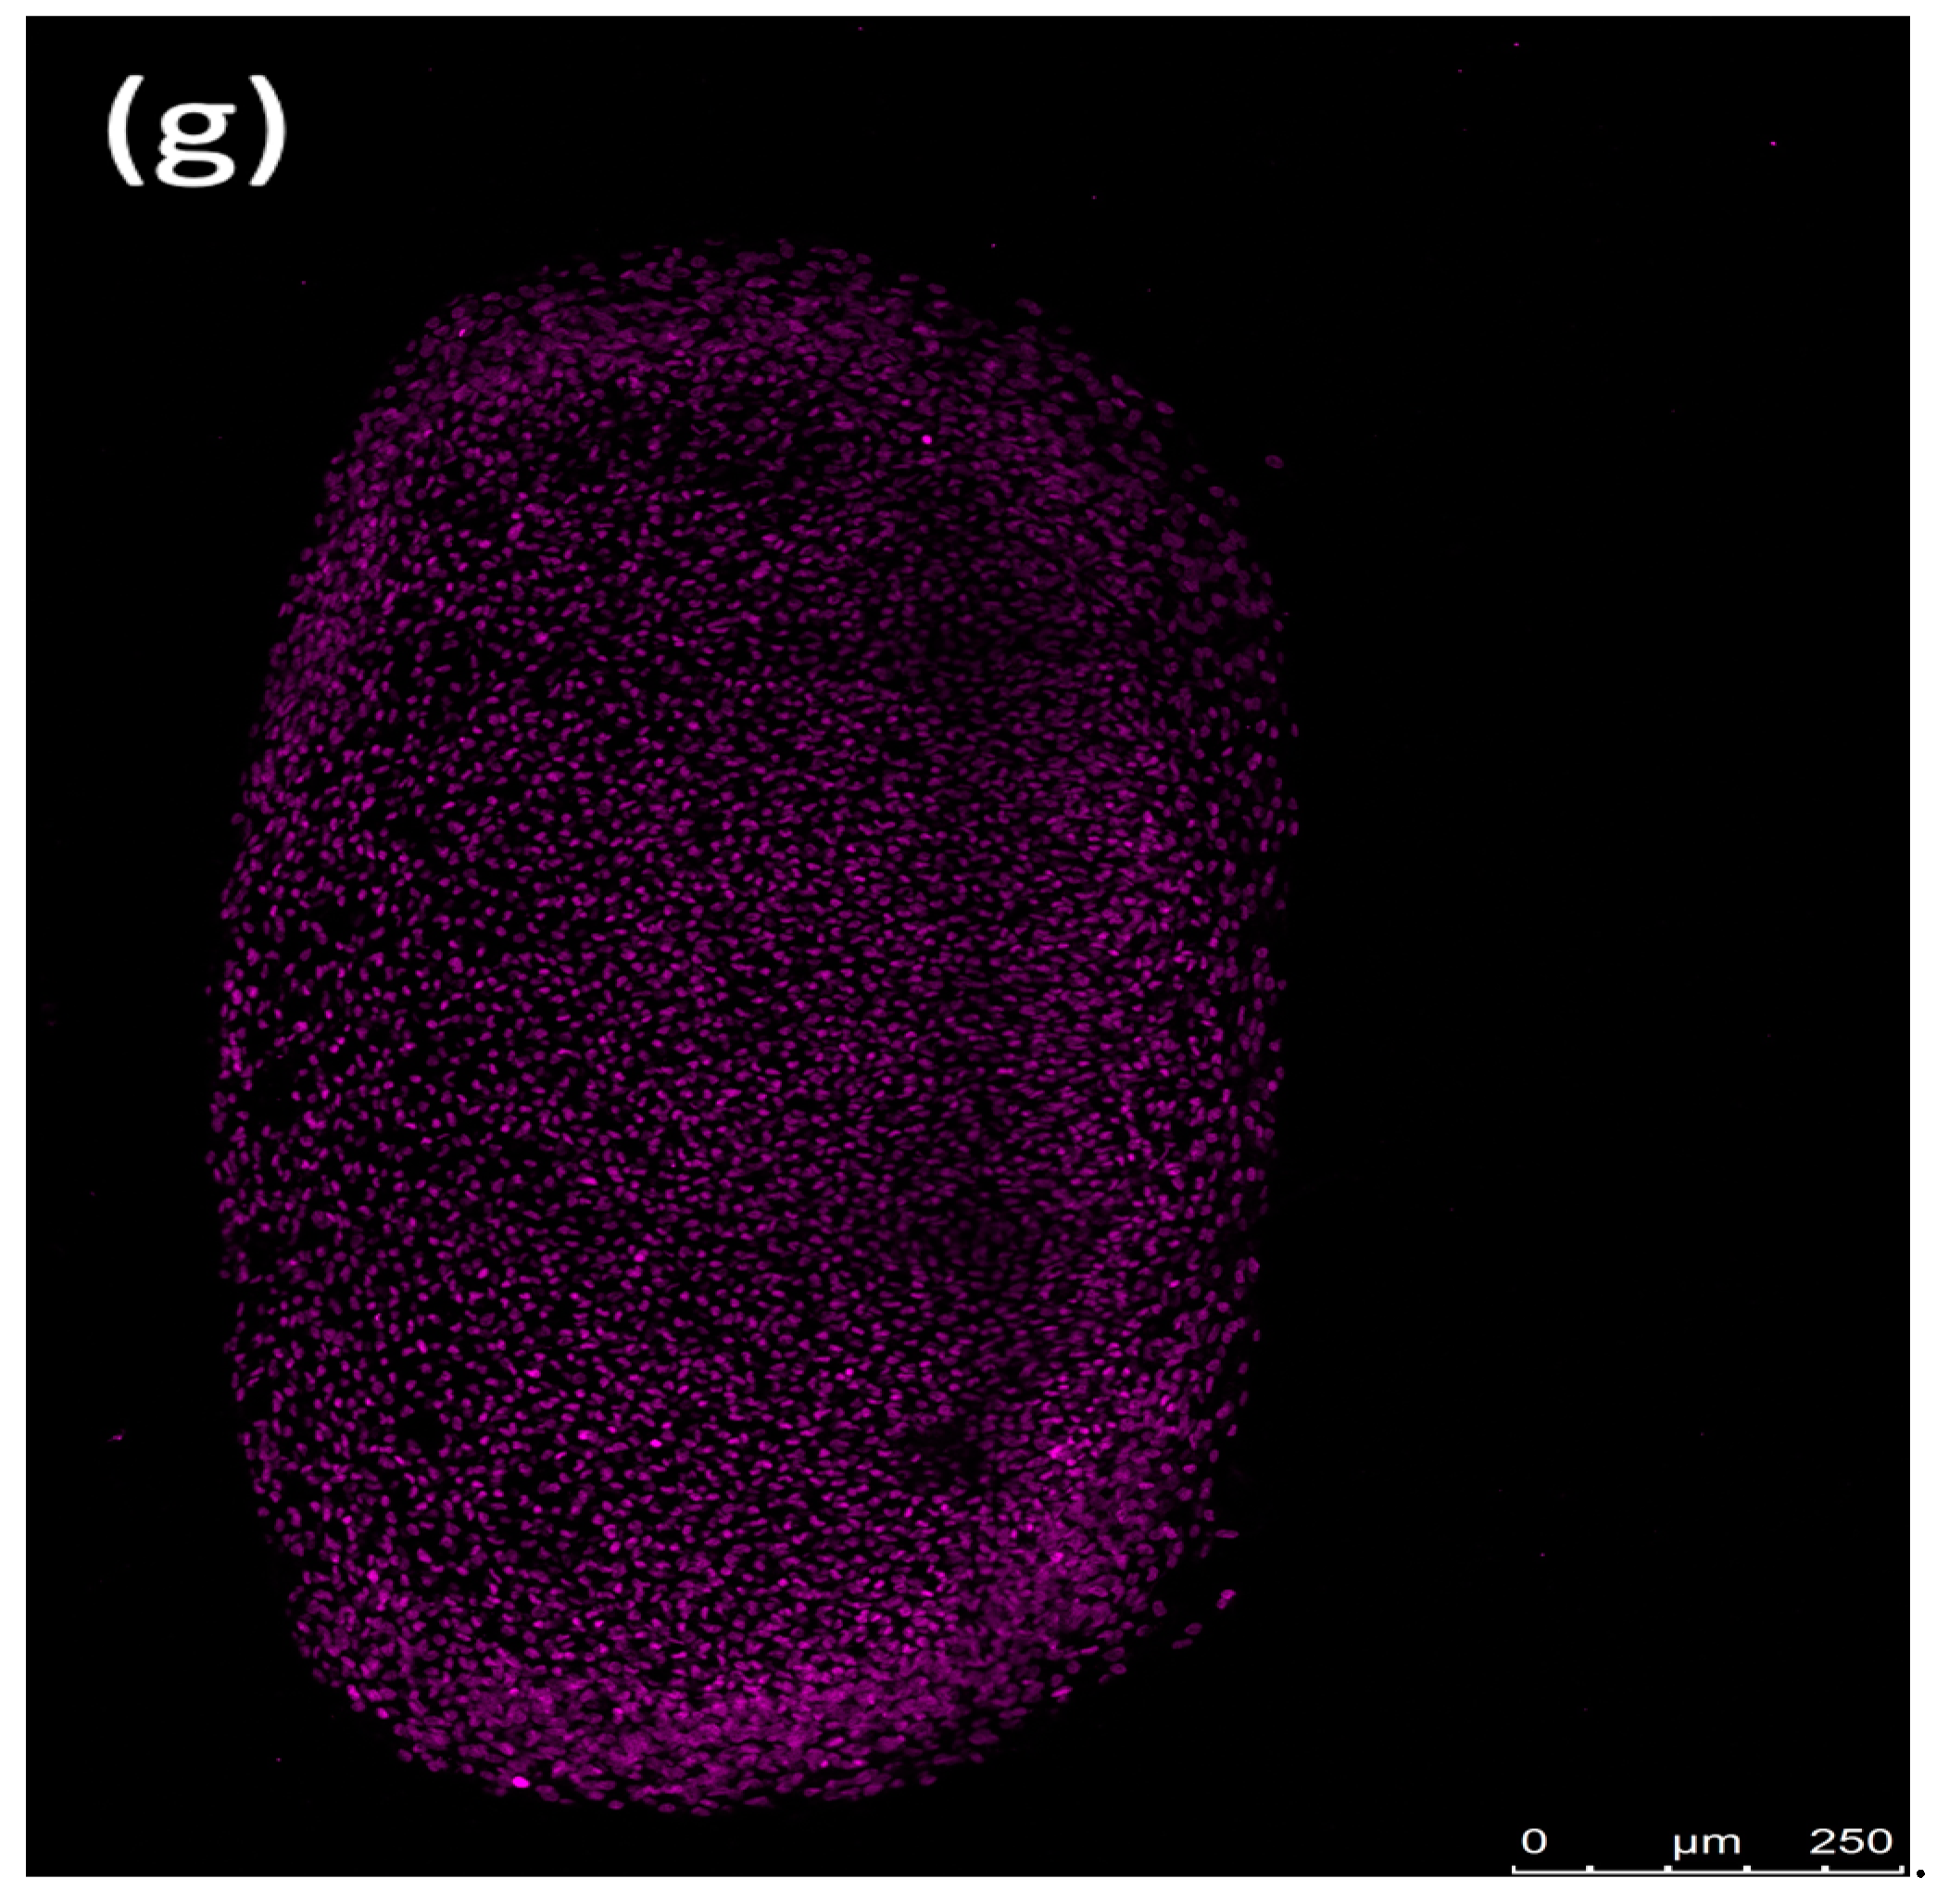

3.2. H&E-Stained Distribution of the Cell Nuclei

3.7. Observing Erythrocyte Influence on Chondrogenic Spheroid Integrity